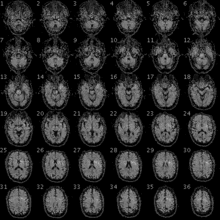

An fMRI image with yellow areas showing increased activity compared with a control condition